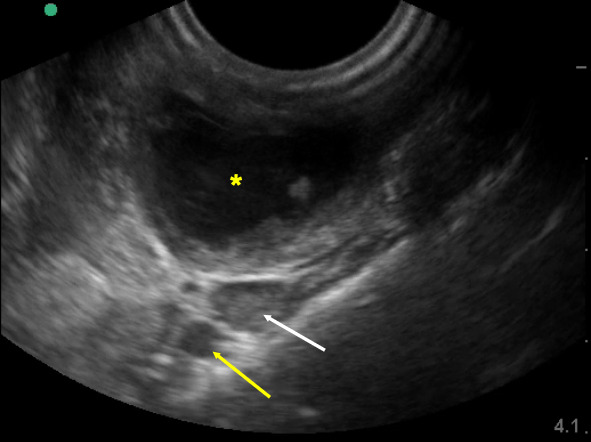

The use of point of care ultrasound (POCUS) for diagnosis and treatment of peritonsillar abscess (PTA) is increasing 1. Proven advantages include improved diagnostic accuracy and treatment success rates as well as decreased otolaryngology consultation, computed tomography (CT) usage, return visits to the emergency department (ED), and length of stay 1. We present a case of a patient with a PTA that was diagnosed and successfully treated utilizing POCUS, avoiding the need for otolaryngology consultation and CT.